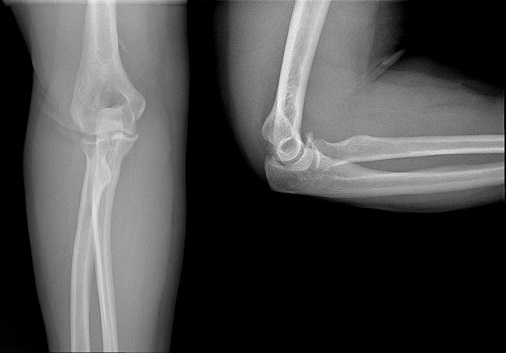

An 80 year old female presents to your office with a left ring finger deformity after a fall one week ago. She initially went to urgent care and xrays were unremarkable for a fracture (Figures 1 and 2). A photo of her left ring finger is shown in figure 3. On physical exam the left ring finger is in hyperextension at the PIP joint and flexion at the DIP joint. She able to flex her PIP joint with full motion. What is the best treatment option?